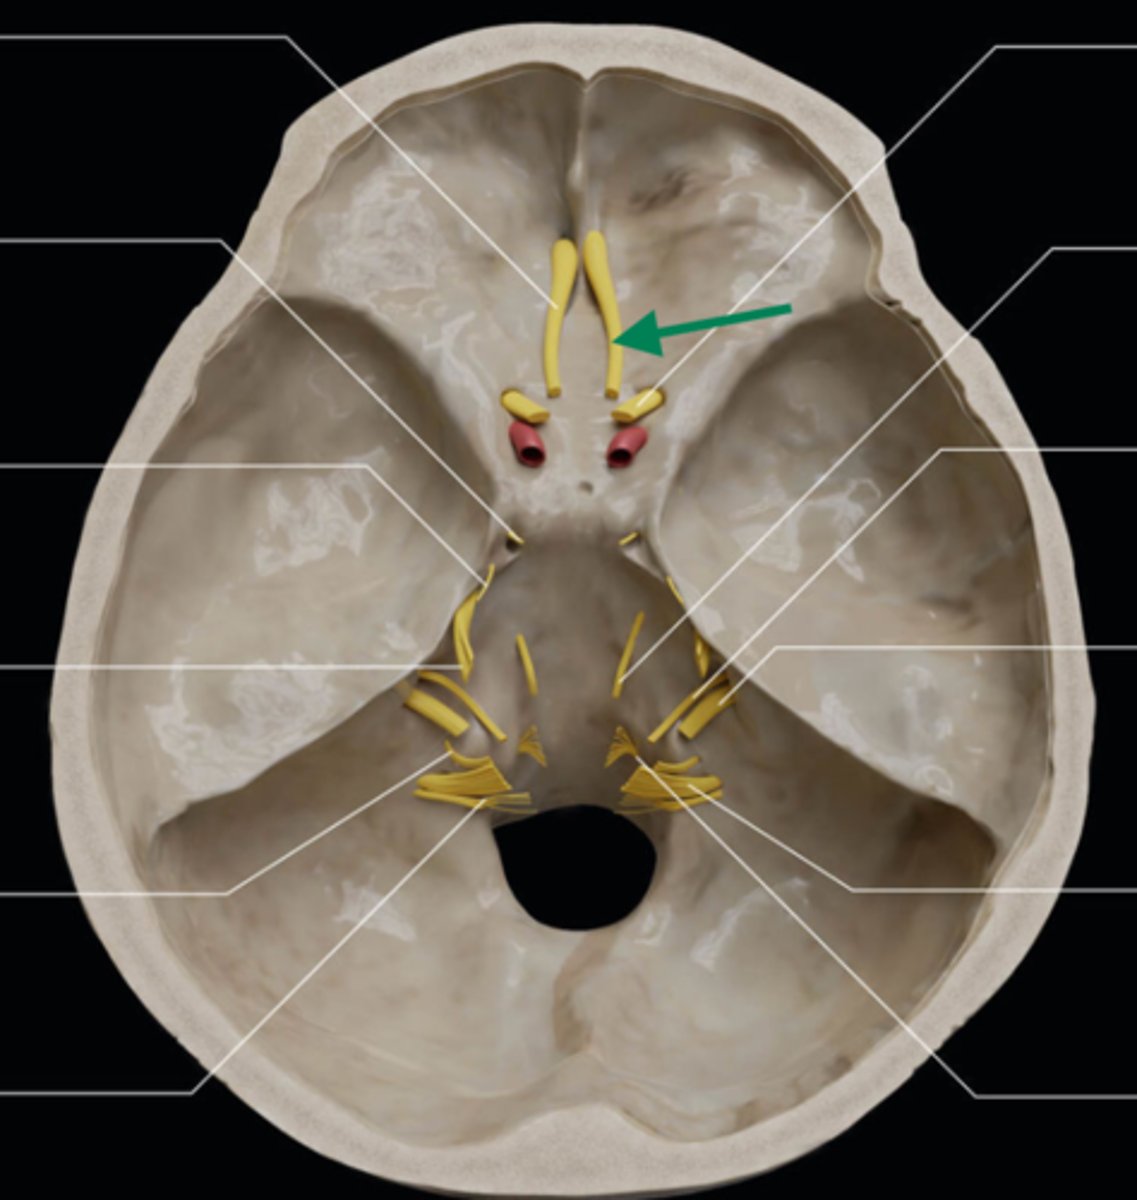

olfactory bulb

olfactory tract

optic nerve (CN II)

internal carotid artery

oculomotor nerve (CN III)

trochlear nerve (CN IV)

abducent nerve (CN VI)

trigeminal nerve (CN V)

facial nerve (CN VII)

vestibulocochlear nerve (CN VIII)

glossopharyngeal nerve (CN IX)

vagus nerve (CN X)

accessory nerve (CN XI)

hypoglossal nerve (CN XII)

optic chiasm

trigeminal ganglion

anterior cranial fossa